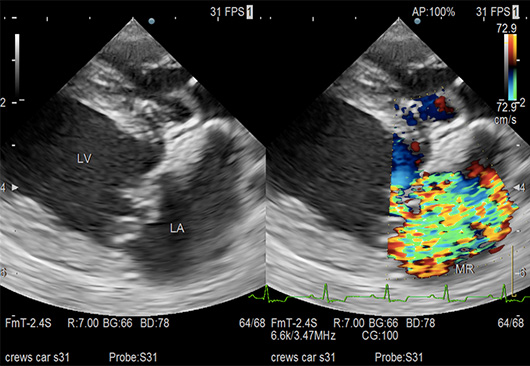

僧帽弁閉鎖不全症(超音波検査)

僧帽弁は左心房と左心室の間にある弁で、血液が一定の方向(左心房→左心室→大動脈)に流れるように働いています。僧帽弁閉鎖不全症とは、この弁が完全に閉鎖せず、血液の一部が左心室から左心房へ逆流してしまう状態をいいます。この逆流が心雑音として聴診でみつかります。